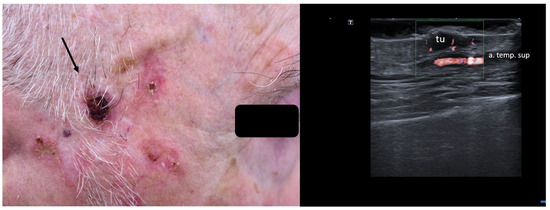

8. Preoperative Neuro-Vascular Mapping

2. Enhancement of Diagnostic Accuracy, Avoidance of Misdiagnosis, Early Identification of Local Relapse